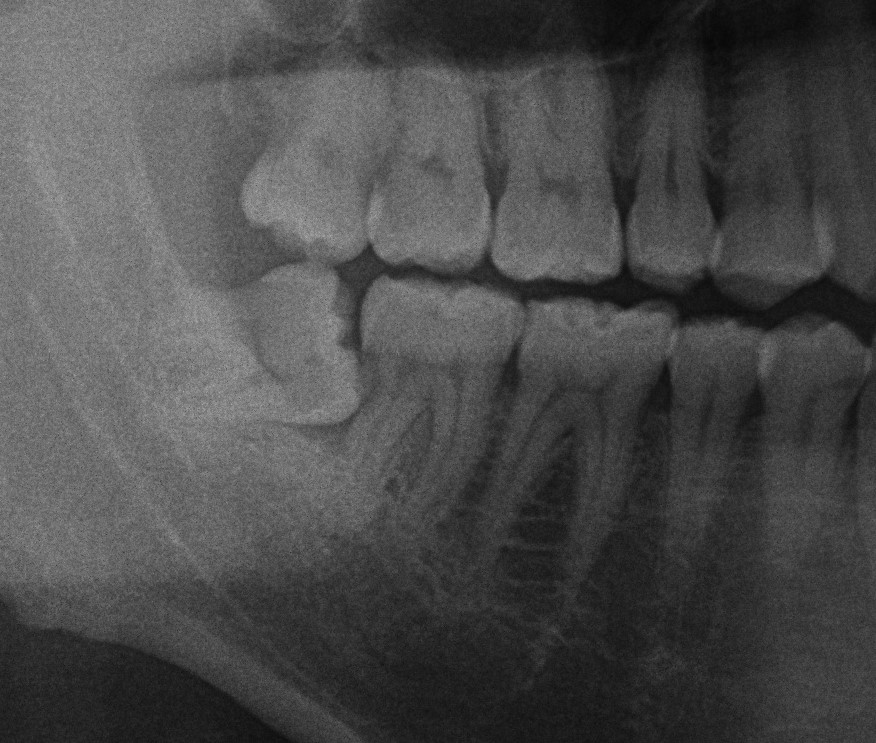

口腔外科、歯根嚢胞について

今回は歯根嚢胞についてお話します。 この写真の方は左上が噛むと痛いとして来院された患者様です。 パノラマでは上顎洞に広がる歯根嚢胞が認められます。 では歯根嚢胞というのはどんなものか説明していきます 概要 病的な袋状のも […]